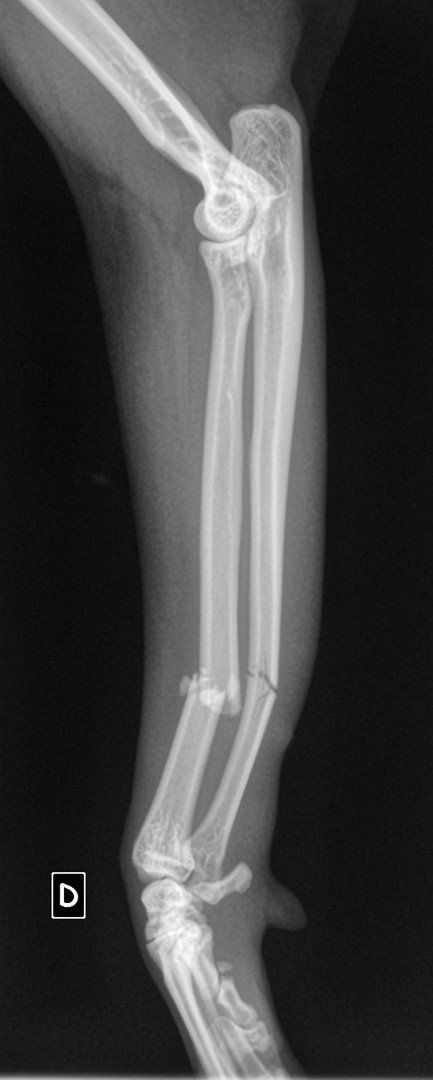

Il a eu le bon réflexe de la déposer chez le vétérinaire du quartier qui a constaté que la petite avait sa patte avant gauche déformée. Il s’est avéré, en grandissant, qu’elle ne se sert pas de sa patte.

Nous l’avons emmené en consultation au CHVA de Beaulieu à Nantes pour avoir l'avis d'un spécialiste. Hélas, il faudra l’amputer car Uanna n’a aucune sensibilité à cette patte. Elle est handicapée et cela devient un fardeau pour elle car Uanna a du mal à se déplacer. Elle s’est blessée plusieurs fois, cela devient urgent pour elle

Coût de l’opération : 1064,20€ (devis en photo)